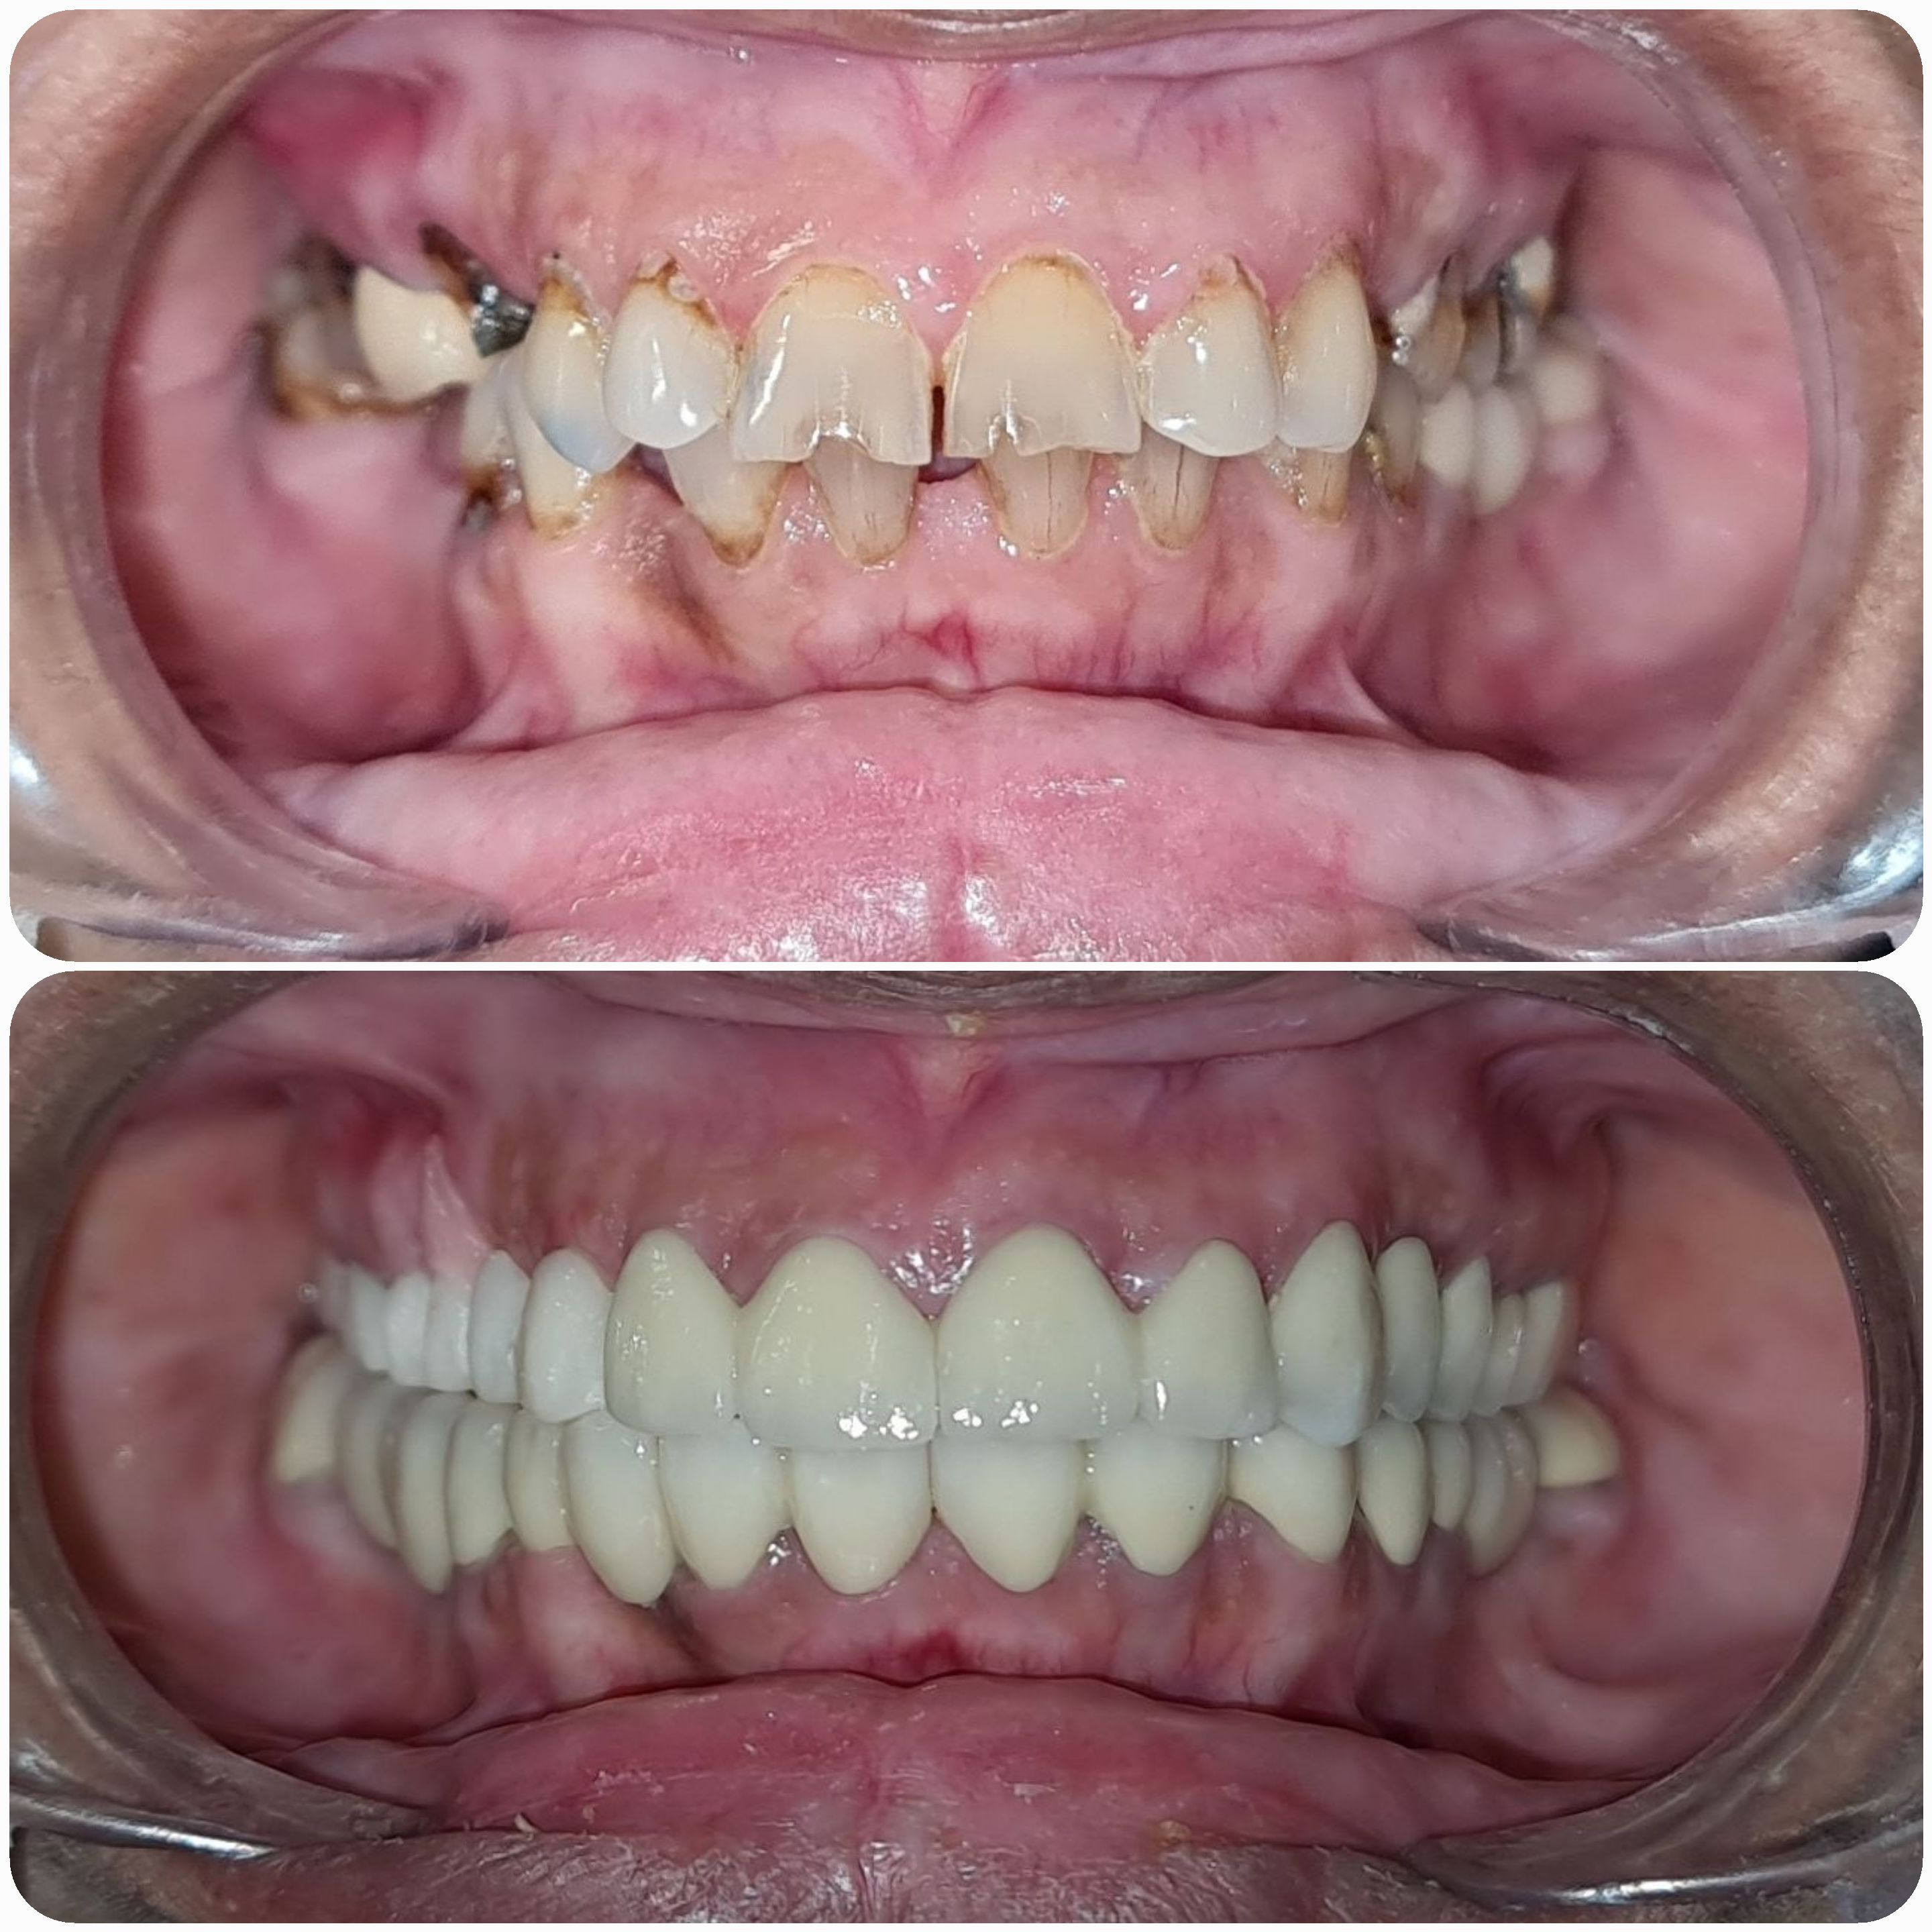

• Cases